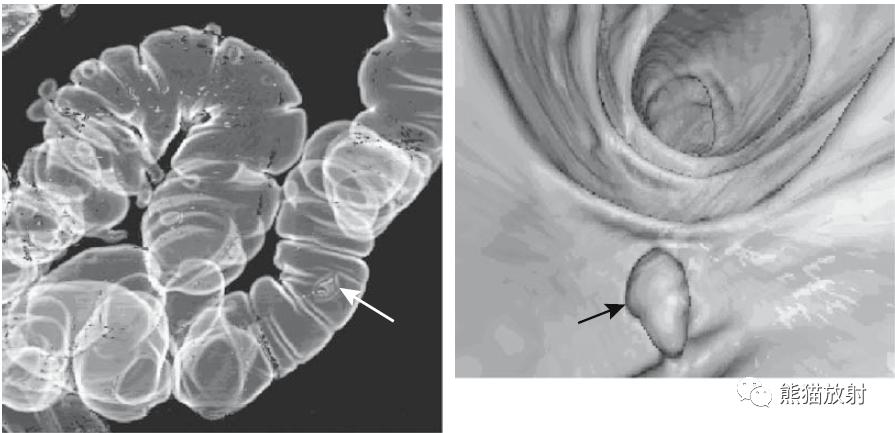

3D CT双对比虚拟结肠镜检查的两个视图。可以从空间上的任何角度来分析图像。

计算机辅助息肉检测。静脉注射造影剂后局灶性肿瘤灌注增加,以自动“检测”潜在的肿瘤(箭头)。

两张3D双对比MR虚拟结肠镜图像。可视化类似于使用CT获得的可视化